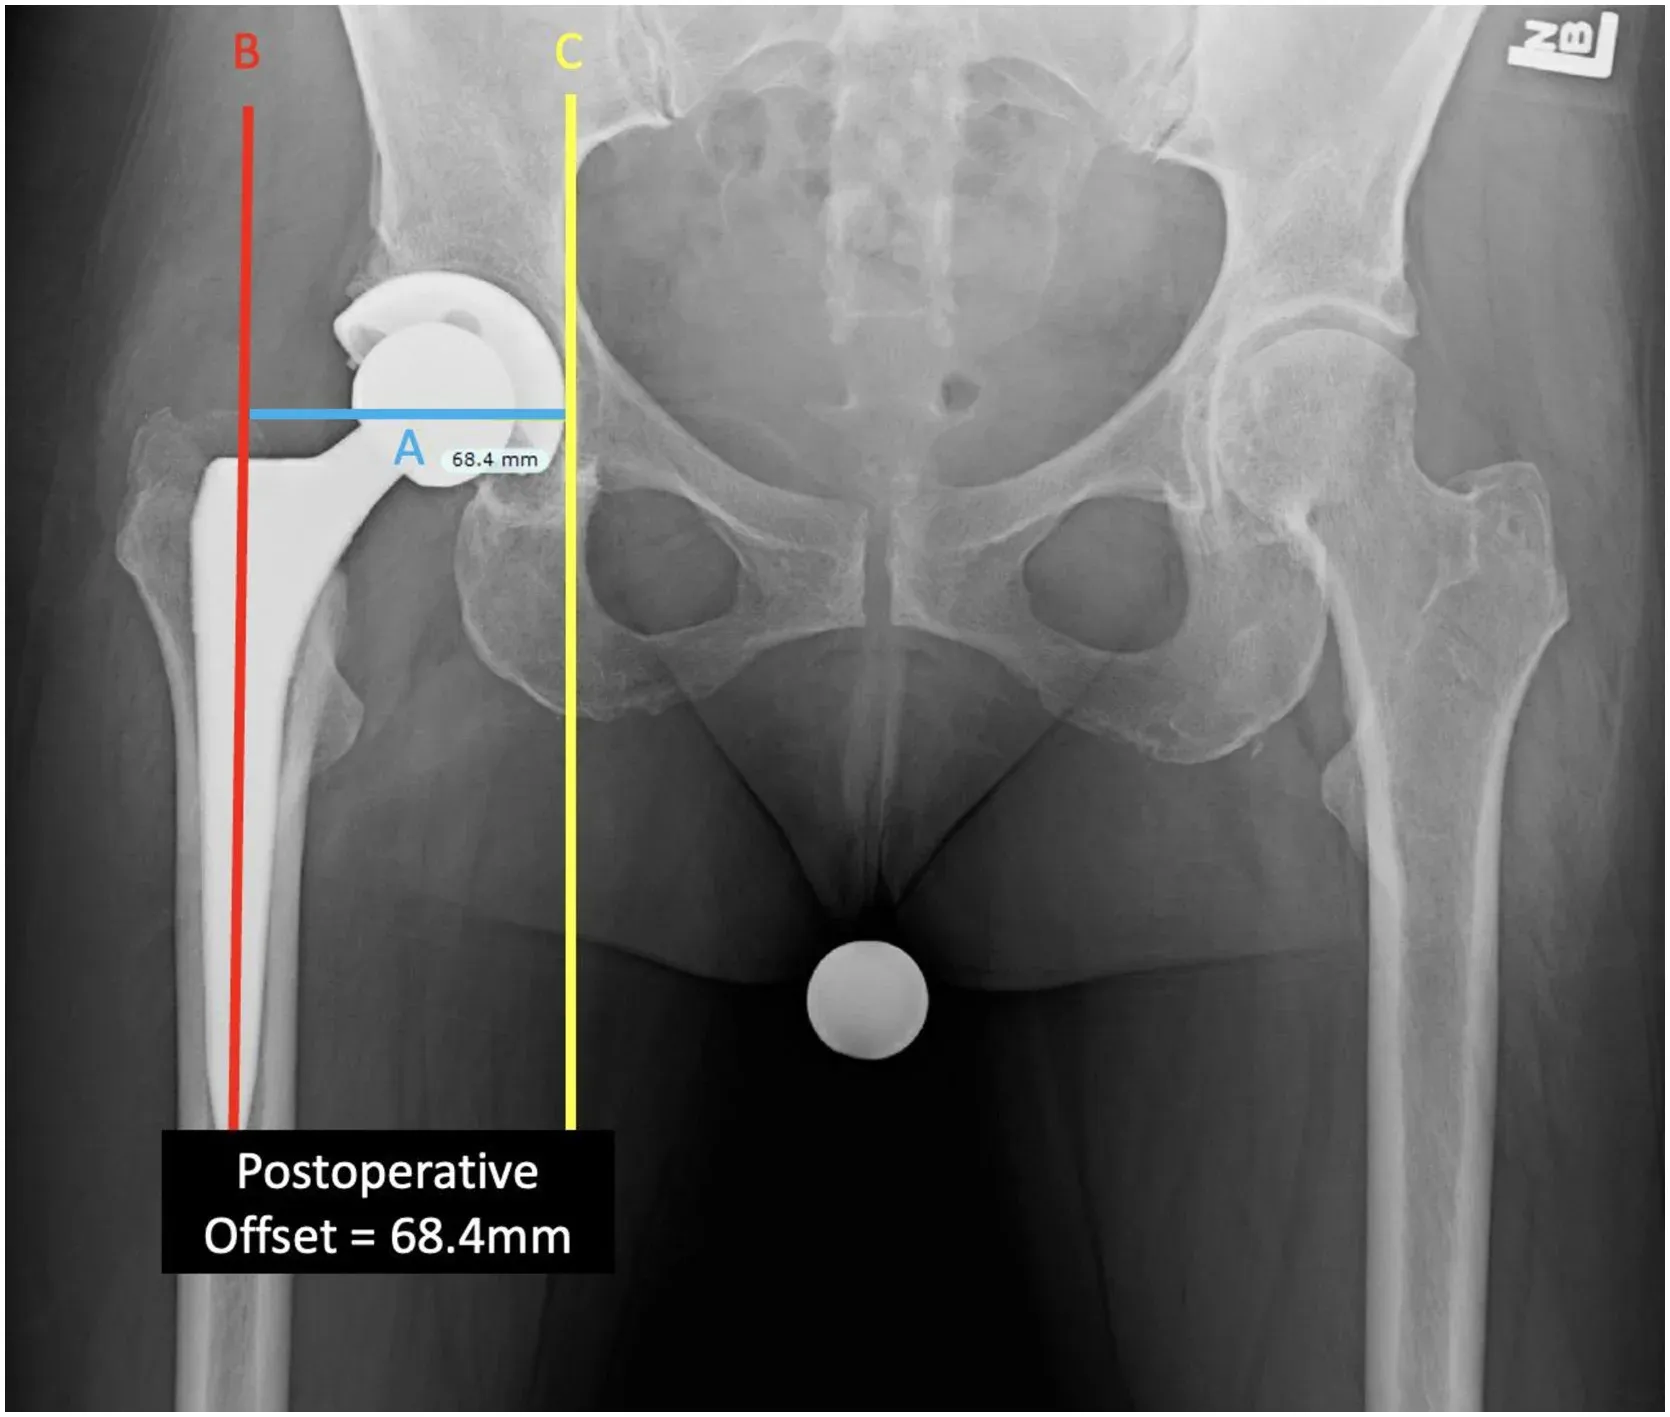

1. Offset in Total Hip Replacement By Dr. Ravinder Dimri

One of the most misunderstood but vital topics in arthroplasty, explained with absolute clarity.

Key Highlights:

🔹 What is “offset” and why does it matter in THR

🔹 How improper offset affects biomechanics and leg length

🔹 Long-term implications for implant stability

🔹 Common mistakes and how to avoid them

🔹 Essential for MS/DNB residents and early surgeons

Click Here to Watch the Video →